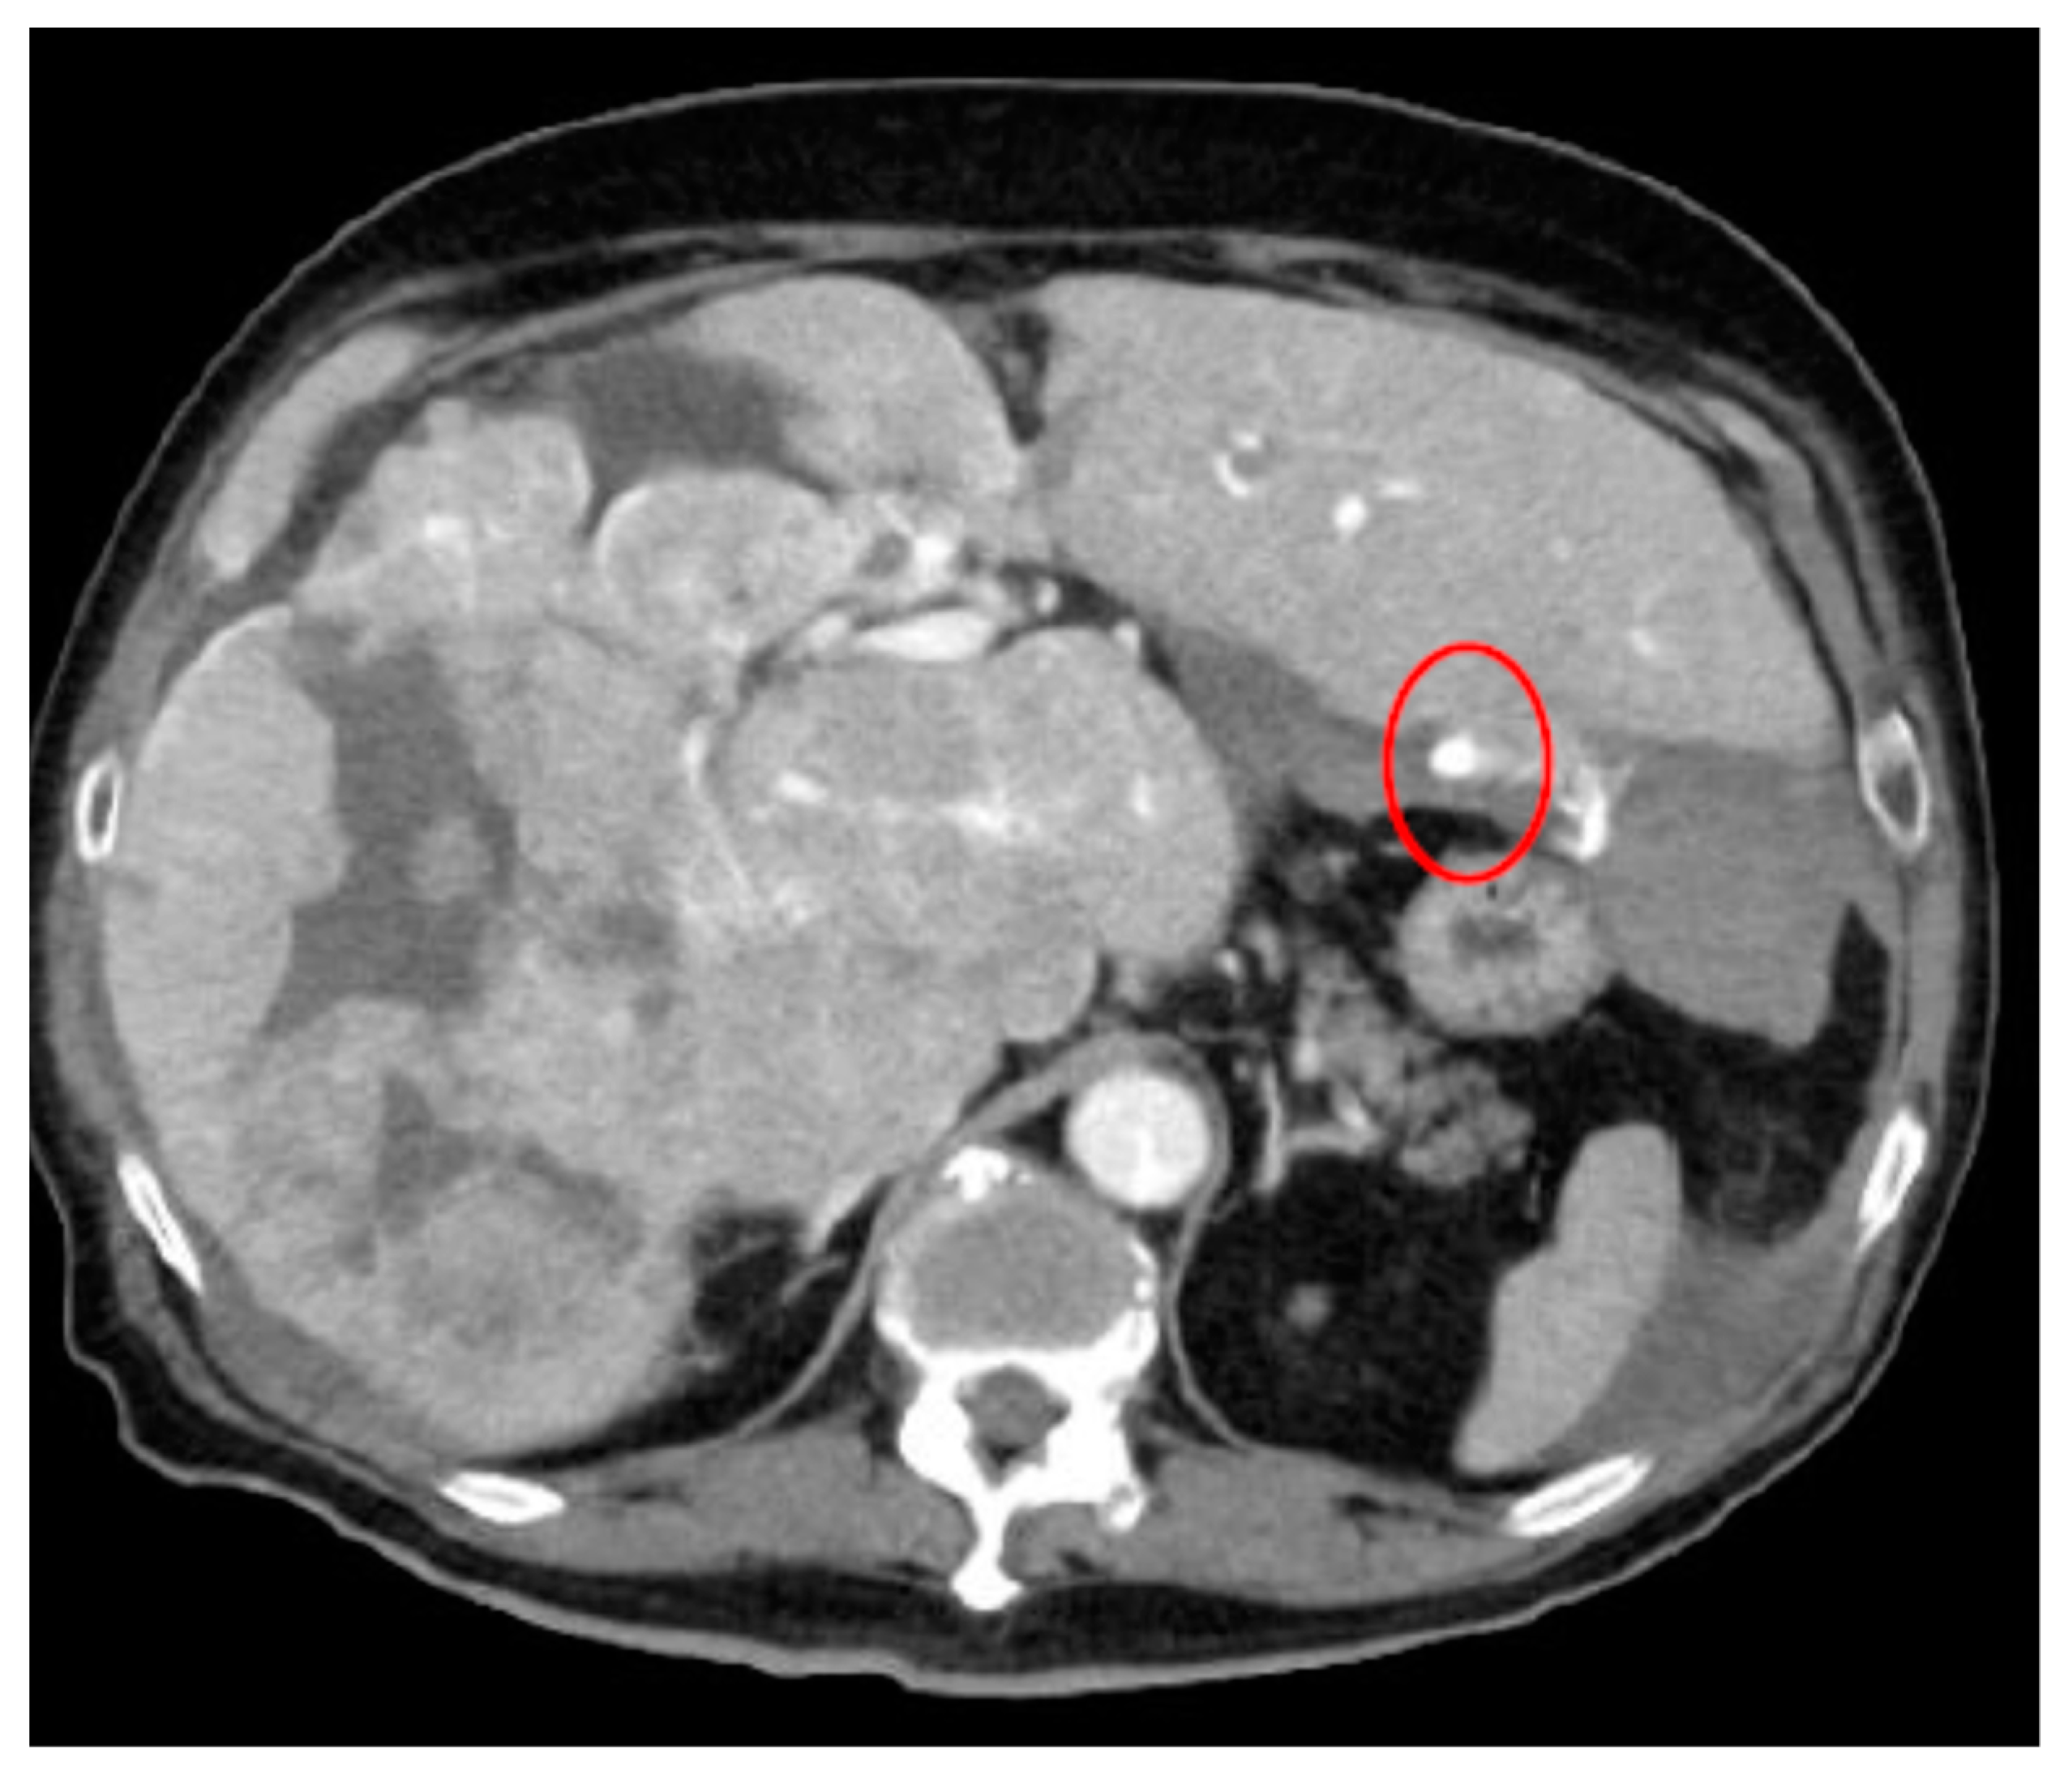

As an example, Figure 1 shows extravasation-induced hemorrhage from a polycystic kidney. Identifying the precise bleeding site on the computed tomography (CT) image presented a challenge. However, upon reviewing the angiography findings, it became evident that the bleeding originated from the area depicted in the CT image. In Figure 2, two instances of extravasation-induced hemorrhage are depicted, marked with the circles. Firstly, (a) displays a pseudoaneurysm visible post-spleen injury. Secondly, (b) illustrates a muscle hematoma in the chest region. In Figure 3, two cases of extravasation-induced hemorrhage are evident. In (a), circles mark extravasation on a fractured pelvic region, indicating a significant injury. Meanwhile, (b) showcases an intragluteal hematoma, highlighting the varied presentations of extravasation across different anatomical contexts. These CT images provide valuable insights into the varied presentations of extravasation cases across different anatomical contexts.

Figure 2.

Extravasation-induced hemorrhage shown with circles: pseudoaneurysm after spleen injury (a), and (b) muscle hematoma in chest.